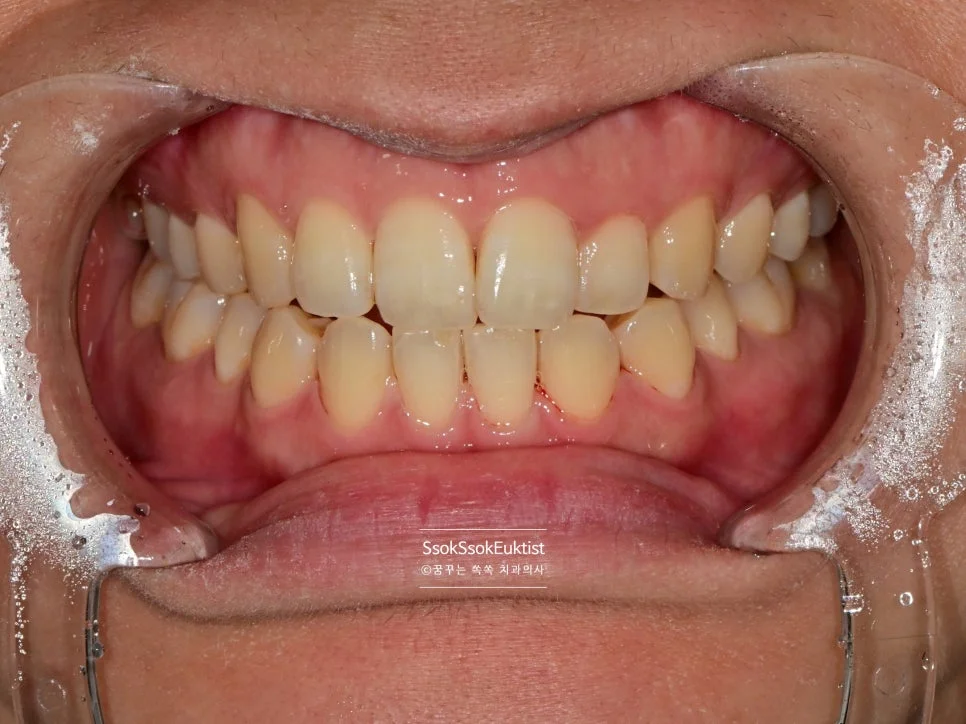

수면 스케일링 후 깨끗한 치아

After — 수면 스케일링 후

왼쪽 위 치경부 우식을 레진으로 예쁘게 치료한 후 스케일링도 시행하였는데요. 비교적 깨끗하고 건강해진 모습이 보입니다~^^